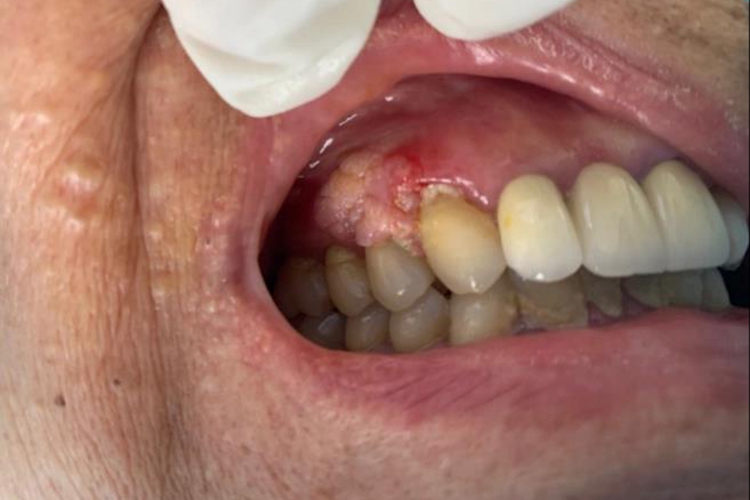

尖锐湿疣的皮损初期表现为局部细小丘疹,针头至粟粒大小,逐渐增大或增多,向周围扩散、蔓延,渐发展为乳头状、鸡冠状、菜花状或团块状赘生物。损害可单发或多发,色泽可从粉红至深红、灰白乃至棕黑。皮损多发生在生殖器及周围皮肤上,另外也可发生于肛周和口腔。